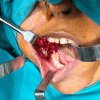

Granular Cell Ameloblastomatous Transformation From the Remnants of a Dentigerous Cyst: A Unique Case Report

Granular cell ameloblastoma is a unique, infrequent histologic variant of unicystic/multicystic ameloblastoma showing distinct histologic and immunohistochemical features. The prognosis and treatment are similar to other common subtypes of solid or multicystic ameloblastoma. Granular cell ameloblastoma should be distinguished from other lesions with granular cells mainly due to its high risk of recurrence. Although it is rare, it has greater recurrence potential and chances of malignant potential. A better knowledge of the molecular pathogenesis of ameloblastoma and its various subtypes may provide diagnostic and therapeutic benefits. We are reporting a case of granular cell ameloblastoma arising from the wall of a dentigerous cyst. The lining of the dentigerous cyst shows a potential for neoplastic transformation to ameloblastoma, squamous cell carcinoma, and mucoepidermoid carcinoma.